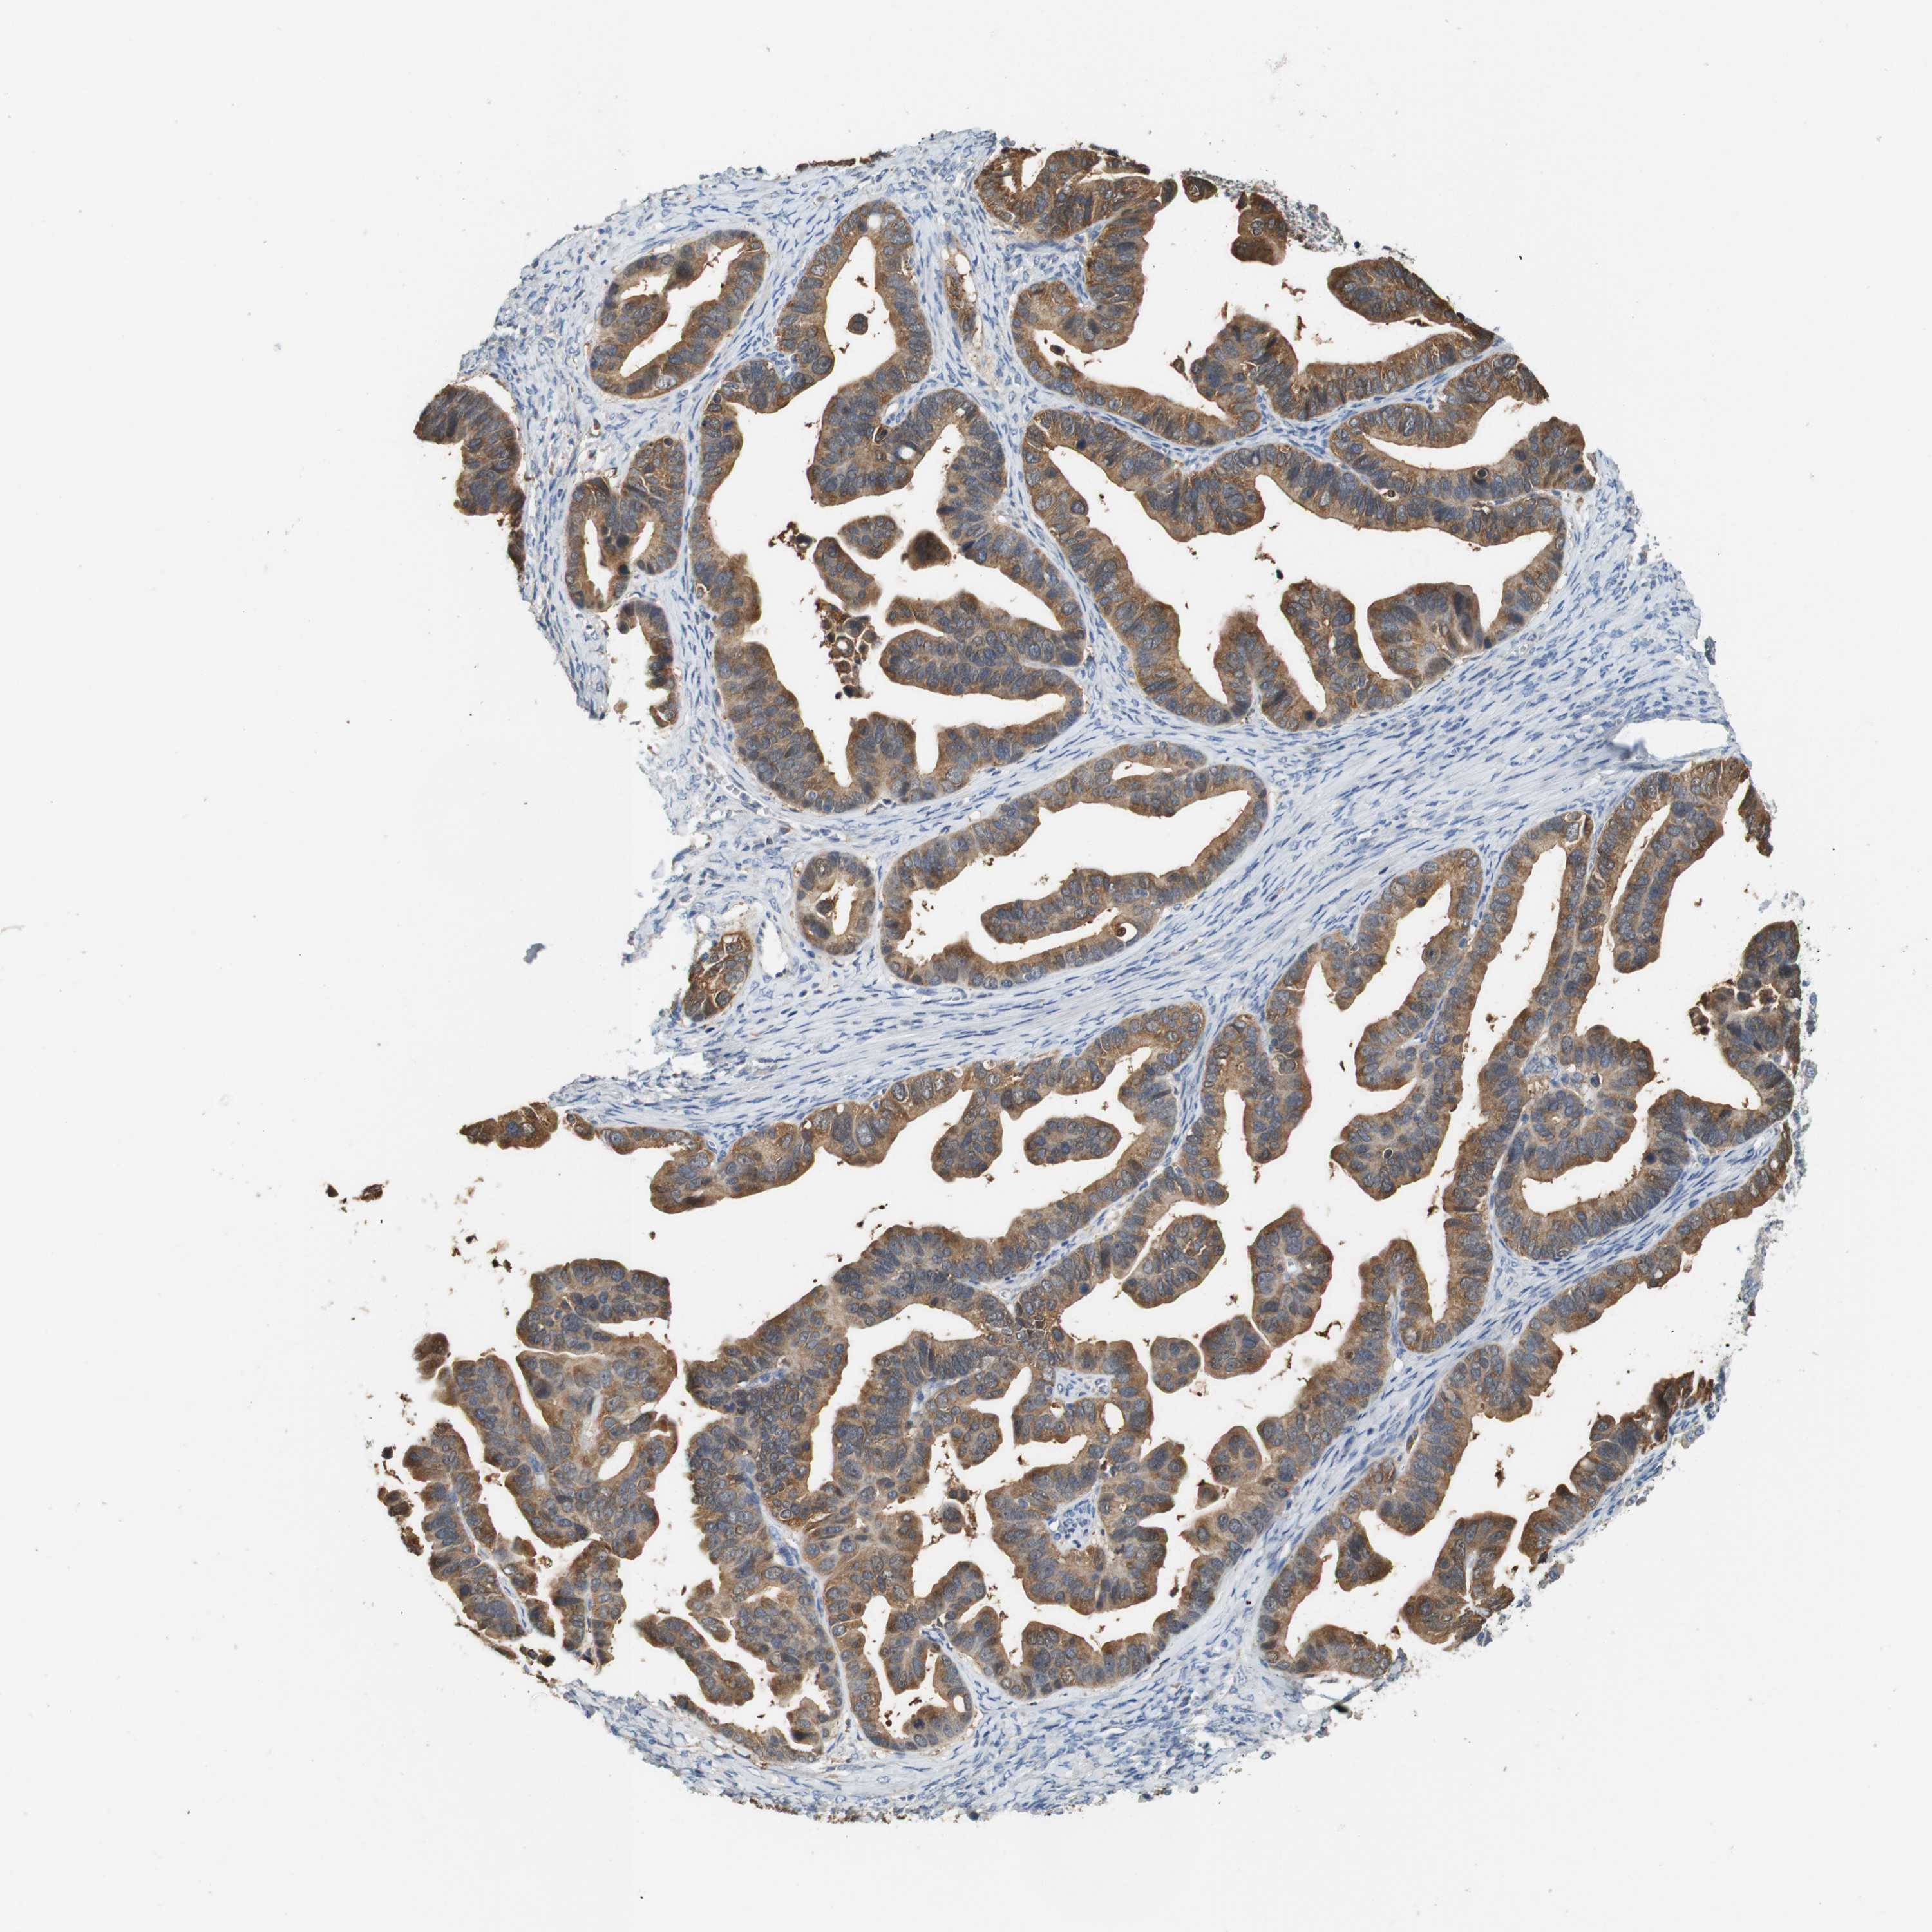

OVARIAN CANCER - Protein expressioni

A mouse-over function shows sample information and annotation data. Click on an image to view it in a full screen mode. Samples can be filtered based on level of antibody staining by selecting one or several of the following categories: high, medium, low and not detected. The assay and annotation is described here.

Note that samples used for immunohistochemistry by the Human Protein Atlas do not correspond to samples in the TCGA dataset.

Antibody stainingi

Antibody staining in the annotated cell types in the current human tissue is reported as not detected, low, medium, or high, based on conventional immunohistochemistry profiling in selected tissues. This score is based on the combination of the staining intensity and fraction of stained cells.

Each image is clickable and will lead to virtual microscopy that enables deeper exploration of all samples and also displays staining intensity scores, fraction scores and subcellular localization as well as patient and tissue information for each sample.

Antibody HPA013994

Antibody HPA013995

Cystadenocarcinoma, serous, NOS

Carcinoma, endometroid

Cystadenocarcinoma, mucinous, NOS

Carcinoma, NOS